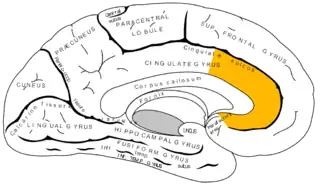

El córtex del cíngulo anterior (CCA) o circunvolución del cíngulo anterior es la parte frontal de la circunvolución del cíngulo, que parece un "collar" formado alrededor del cuerpo calloso, el mazo fibroso que transmite las señales neuronales entre los hemisferios cerebrales derecho e izquierdo. Consiste de las áreas de Brodmann 24, 32, y 33. Parece que juega un rol en una gama amplia de funciones autónomas, tales como regular la presión sanguínea y el ritmo cardíaco, como también para ciertas funciones cognitivas racionales, tales como la inhibición verbal, la anticipación de premio, la toma de decisiones, la empatía[1] y las emociones.[2][3]

![]() Superficie medial del hemisferio cerebral izquierdo, con el cíngulo anterior resaltado. | ||